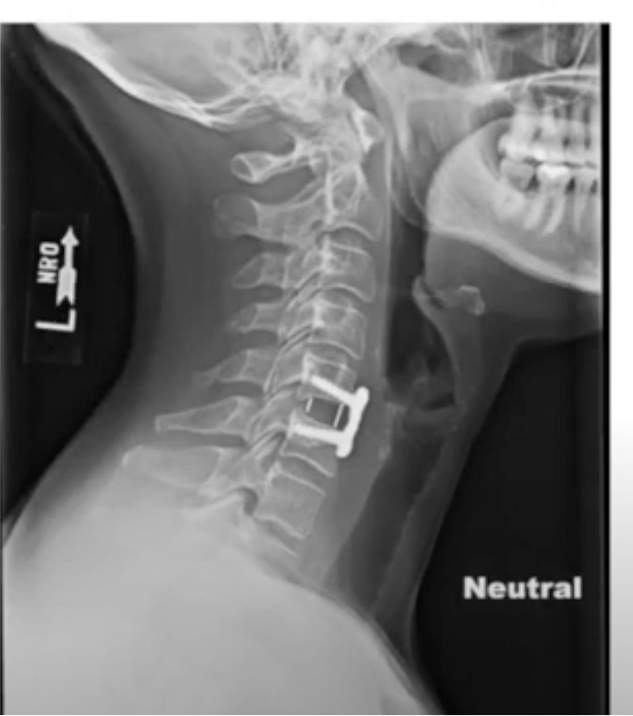

During the procedure, the affected disc or discs are removed from the front of the neck (anterior approach), and a bone graft and possibly a metal plate or cage are inserted to stabilize the spine and promote fusion between the adjacent vertebrae. ACDF may be performed at one or more levels of the cervical spine, depending on the location and severity of the spinal condition.

5. Hardware Placement: Metal plates, screws, or cages may be used to stabilize the spine and facilitate fusion.

– Restoration of spinal stability and alignment